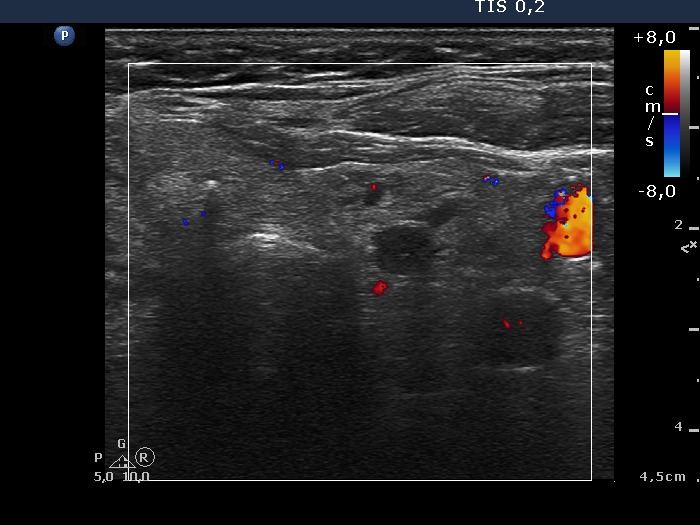

100 consecutive patients with thyroid nodule - Case 26.

8 months after sclerotherapy (ultrasonographic picture 6)

Left lobe, horizontal scan, color Doppler mode.